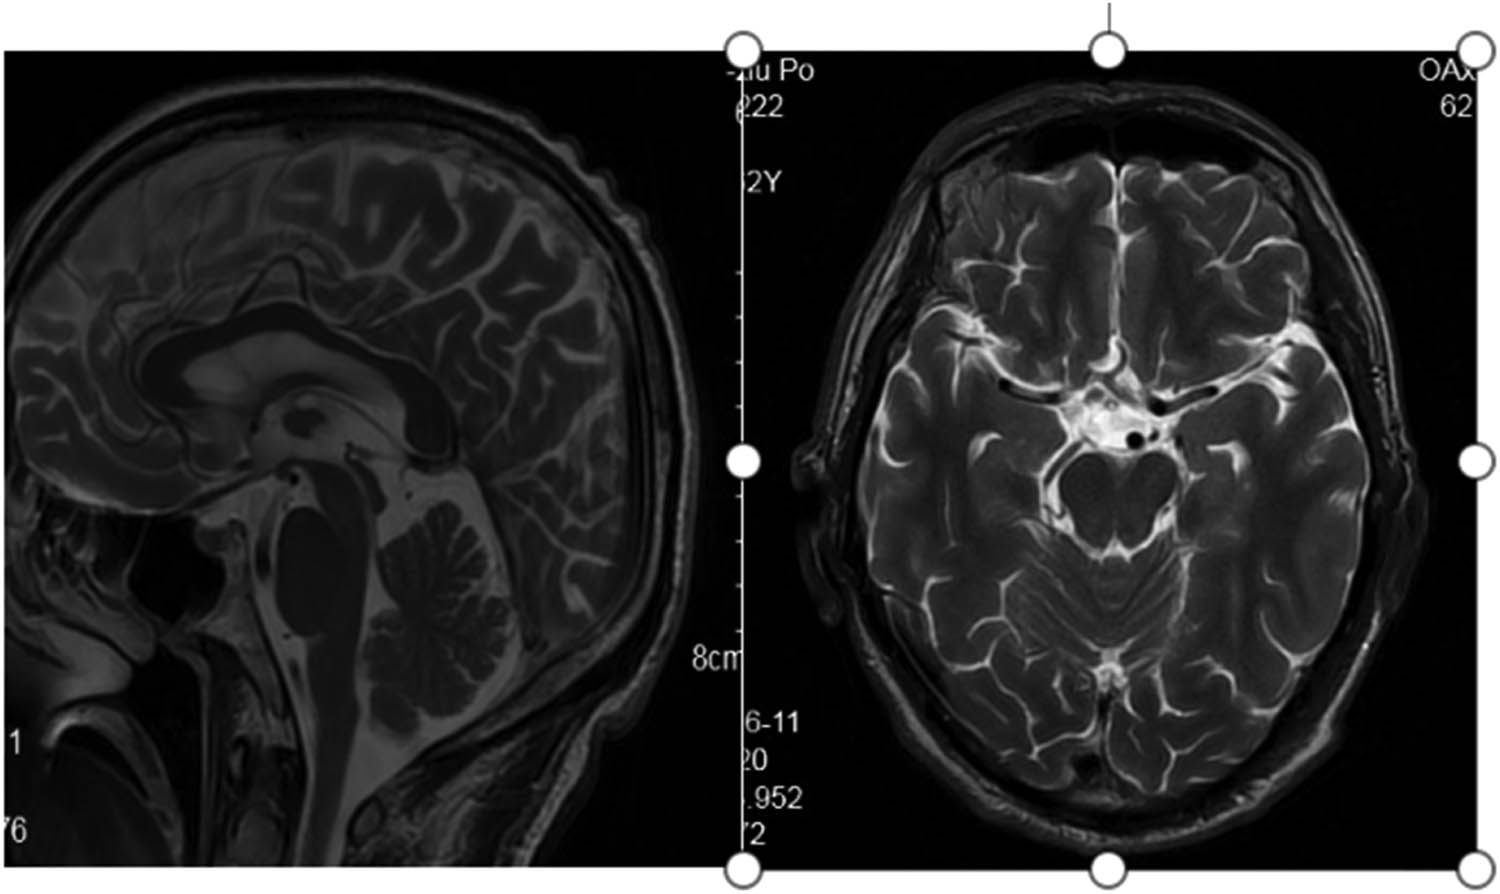

The pedigree of this research is shown in Figure 1. The proband (II-3) is a 61-year-old male who suffered from hypothyroidism and cervical spondylopathy. Two years ago, he experienced shaking of his right hand in a static state, and the shaking was aggravated when he was nervous, accompanied by unresponsiveness. One year ago, he developed speech and swallowing disturbances, and occasionally choking on drinking water. Physical examination revealed involuntary shaking of the right upper limb and clumsy fast alternating hand movements. MRI showed mild cerebellar and pons atrophy (Figure 2). The Mini-Mental State Examination (MMSE) score is 20/30 points (with high school degree). The Hamilton Anxiety Scale (HAMA) score was 16 points, affirming the state of anxiety. A score of 21 on the Hamilton Depression Scale (HAMD) confirmed depression. The Assessment and Rating of Ataxia (SARA) score was 18/40 (Table 1). Inventory of Non-Ataxia Signs (INAs) scored 7 points (Table 2), among which hyperreflexia, spasticity, rigidity, chorea/dyskinesia, dystonia, resting tremor, and cognitive dysfunction were positive. This suggests that the non-ataxia symptoms of the proband are also obvious. Genetic testing of the proband showed a missense mutation in the CCDC88C gene located at 14q32.11 (Figure 3). This mutation is c.1886G > A, so the encoded amino acid changes from arginine to glutamine. The proband’s parents were dead. After detailed inquiry, the parents did not show similar clinical manifestations. The genetic tests revealed heterozygous mutations in the gene CCDC88C in five of the proband’s families (Figure 3), but none of them showed any clinical manifestations so far. The five carriers are as follows: Individual II-2 (the sister of the proband), a 57-year-old female; Individual III-4 (the son of the proband), a 28-year-old male; Individual III-5 (daughter of the proband), a 30-year-old female; Individual IV-1, a 6-year-old boy and Individual IV-2, a 3-year-old boy.

Flat pons, not full and mild cerebellar atrophy in T2-weighted MRI.

From the perspective of imaging, SCAs can be divided into three categories: simple cerebellar atrophy, olivopontocerebellar atrophy, and whole brain atrophy [12]. The degree of cerebellar atrophy matches the severity of ataxia [36]. Theoretically, the severity of cerebellar atrophy can be predicted through the SARA score. Although different subtypes tend to have different locations of atrophy, in general, cerebellar atrophy is the initial stage of intracranial lesions, gradually developing to structures outside the cerebellum, and eventually involving the whole brain.